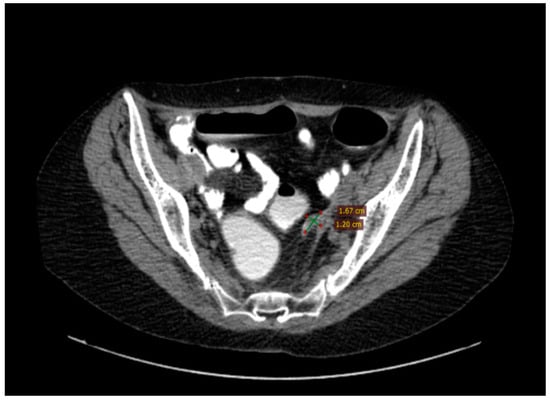

2.2.6. Follow-Up

2.2.7. Compliance